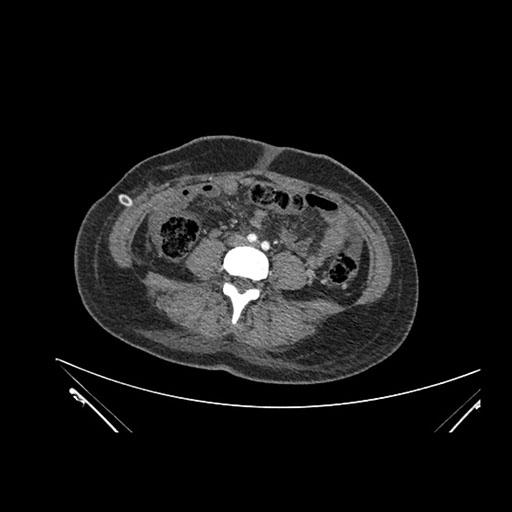

Imaging Analysis

Look through the patient's CT scan to identify any areas of concern for the necessary procedure.

Axial Arterial

Axial Venous

Based on initial findings, which issue(s) would you be most concerned about?